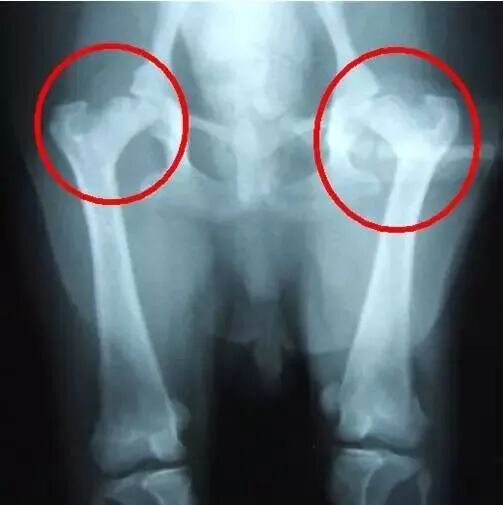

对于一个出生的婴儿,我们的骨科医生将进行初步研究,关于脊柱、四肢,特别是“髋关节”检查的重点是发现“先天性髋关节发育不良”这个隐患。由于这种疾病一旦出现干预越早预后越好成本越低

因此,家长应注意观察婴儿的下肢状况、臀部线条和下肢活动状态。如有疑问应及时请专业骨科医生判断以免延误干预时间